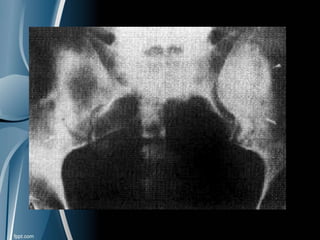

AFECTACIÓN AXIAL

Sacroileitis en el 30% de los px

Asimétrica o unilateral

Grandes sindesmosfitos no marginales y

asimétricos

Articulaciones interapofisarias con

erosiones y anquilosis.

RADIOLOGÍA: AFECTACIÓN AXIAL Sacroileitis en el 30% de los px Asimétrica o unilateral Grandes sindesmosfitos no marginales y asimétricos Articulaciones interapofisarias con erosiones y anquilosis.

• #30 Sacroileitis bilateral asimétrica. Esclerosis subcondral, disminución de espacio articular, pérdida de definición del hueso subcondral por reabsorción ósea y superficies articulares de contorno irregular por la presencia de erosiones.